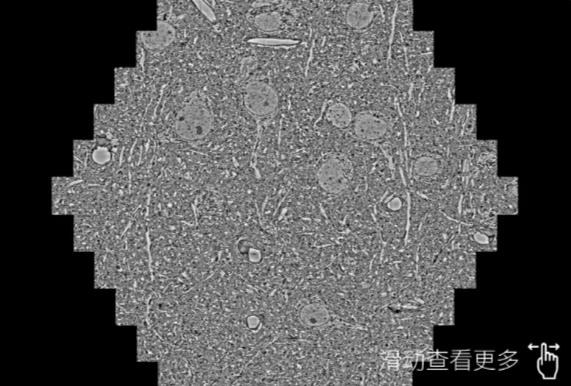

鼠脑切片。左图使用青浦蔡司青浦扫描电镜MultiSEM706对165μmx143pm面积区域成像,耗时仅需1.5秒。右图为鼠脑切片中30μm区域放大效果。样品由芝加哥大学B.Kasthuri提供。